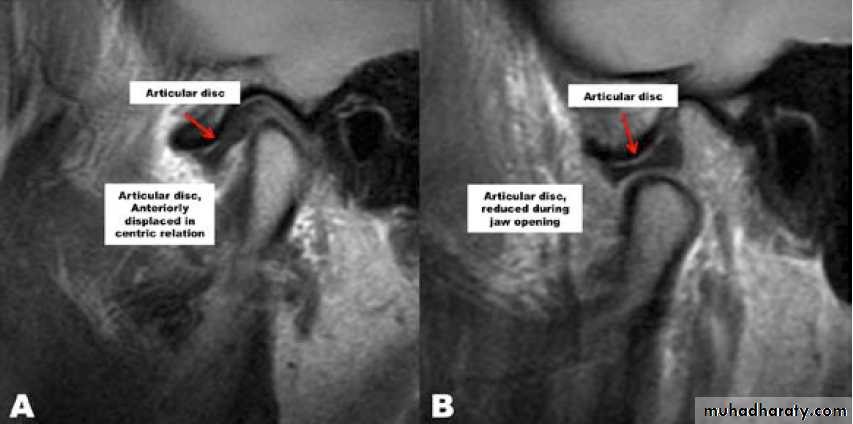

A clinical diagnosis of suspected internal derangement might lead to a requirement for imaging of the disc. This is done by magnetic resonance imaging (MRI).

- The articular disc normally sits above the anterior aspect of the condylar head.- A disc may be anterior to this ‘normal’ position in asymptomatic individuals, suggesting that an anterior disc position is a normal variant. Thus, an internal derangement is best thought of as an abnormality in position that interferes with function and that may be associated with other symptoms.

• An anterior disc ‘displacement’ during closure of the jaw is the most common internal derangement, but anteromedial, medial, and anterolateral displacements are all seen.

Disc displacement with reduction

Reduction means that a displaced disc ‘reduces’ into a normal position on opening but reverts to an abnormal position on closing (reciprocal click).Clinical features

• Clicking on opening (after about 10 mm).

• Clicking on closing.

• Transient jaw deviation during opening/closing.

Radiology

No abnormalities are apparent on plain radiographs. MR imaging shows the displaced disc in a closed/ rest position ( nothing is indicative, but real time MRI) is helpful.